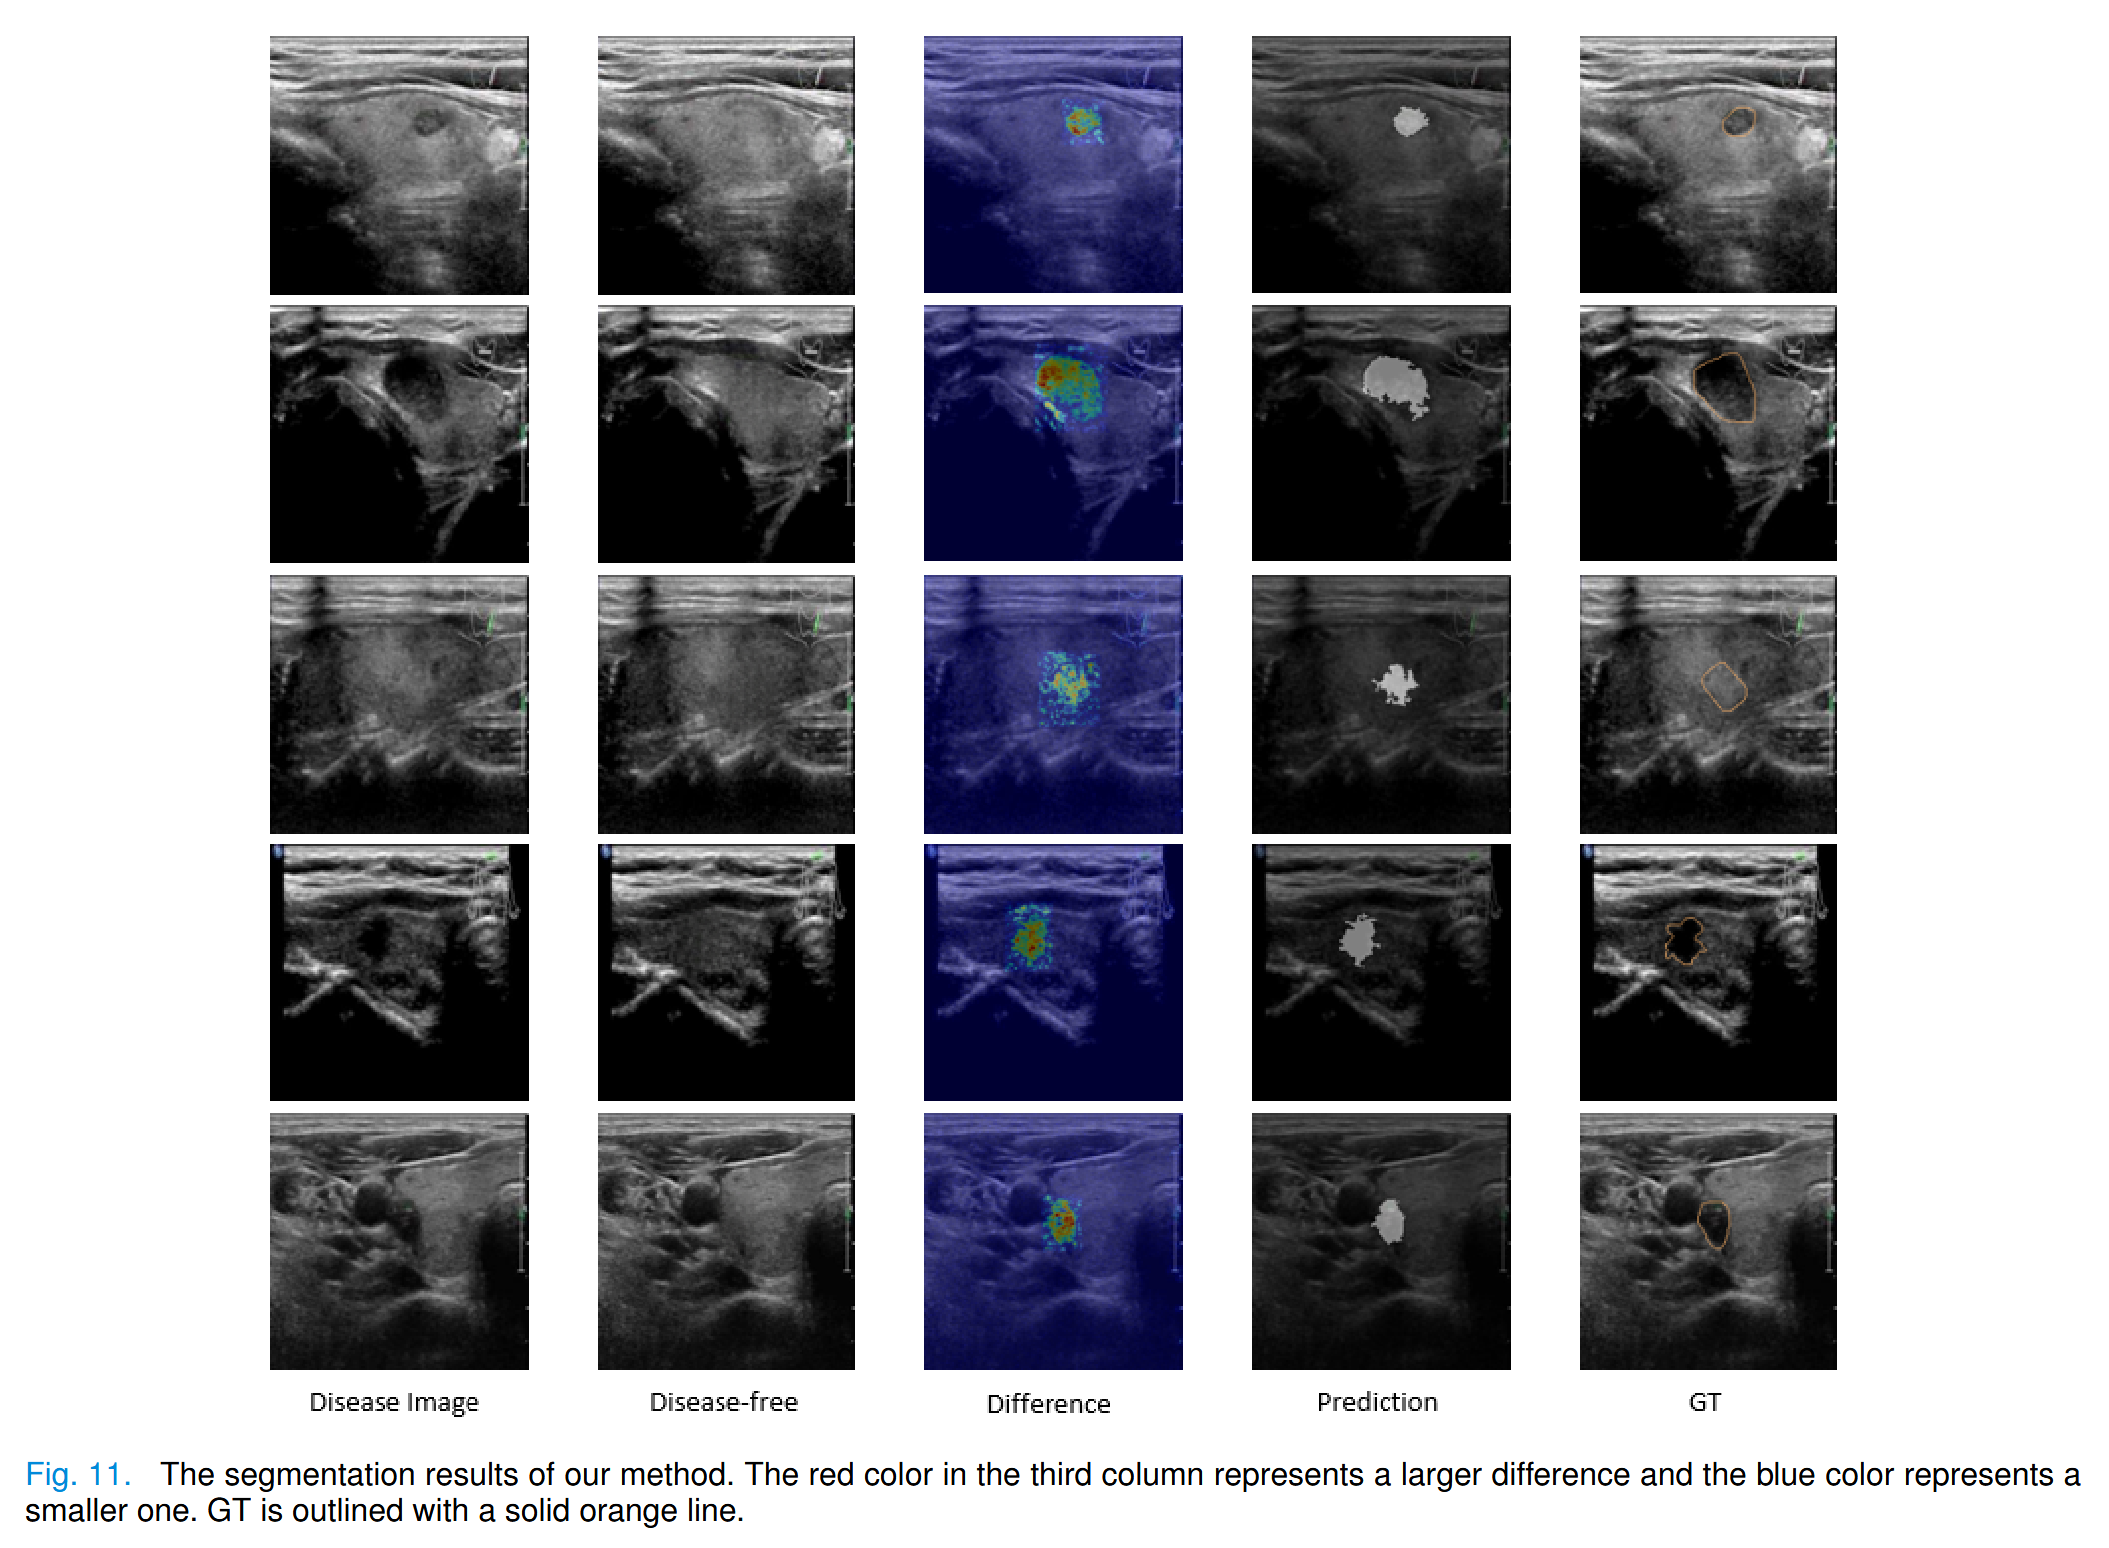

4.4 Weakly supervised segmentation

完成了基于严格点标注的弱监督病灶分割任务。

当疾病图像中的病灶被修复为正常组织时,原始图像与生成图像之间的差异绝对值可以表示像素的异常程度,即病灶的存在。

通过设定阈值为0.1,将这一差异转化为二值预测,如图11所示。

此外,我们与其他弱监督分割方法进行了IOU和Dice的比较,结果表明我们的方法表现更优,如表V所示。

CAM [40] 表示在弱监督分割任务中生成种子点的方法,

CIAN [41] 则是基于优化CAM的重新训练方法。

这两种方法的阈值均设置为0.6。